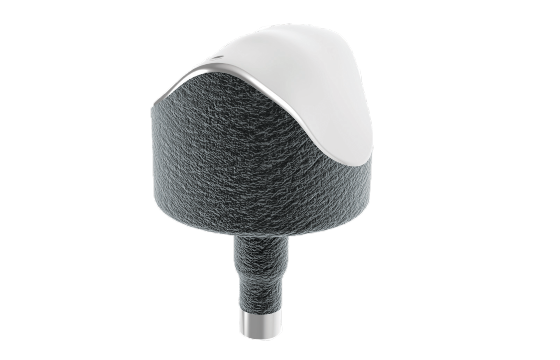

Episealer® Talus

The Episealer Talus is an individualised resurfacing implant intended for use on either the medial or lateral talus. It aims to treat patients suffering from pain and reduced mobility due to focal osteochondral lesions in the talus. The Episealer technology restores the damaged joint surface in order to alleviate pain and quickly enables patients to recover joint mobility.

The Episealer Talus is available in a diameter of 15 mm.